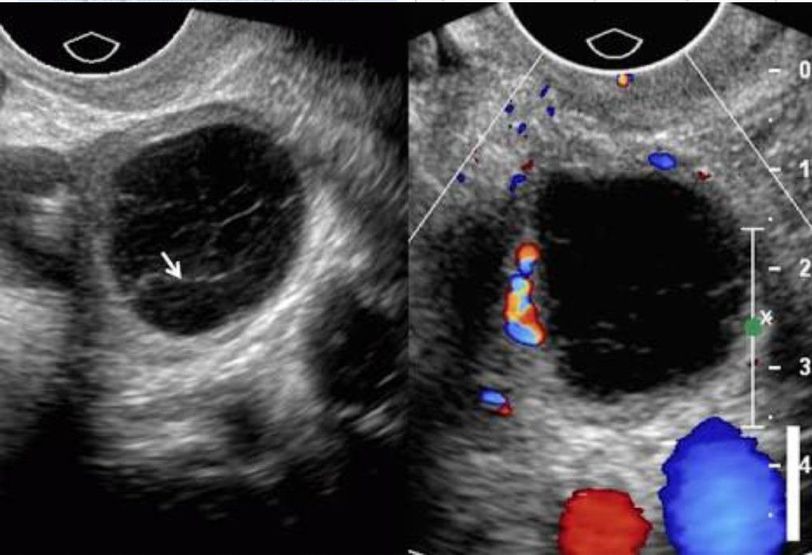

An adnexal mass is a lump in tissue of the adnexa of uterus (structures closely related structurally and functionally to the uterus such as the ovaries, fallopian tubes, or any of the surrounding connective tissue).Adnexal masses can be benign or cancerous, and they can be categorized as simple or complex.